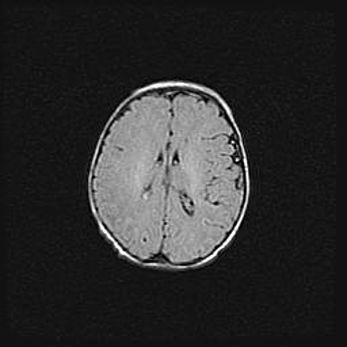

Церебральная ишемия II.

Возраст: 5 дней

Вес: 3400 г

Пол: женский

Окружность головы: 35 см

Срок гестации: 39 недель

Церебральная ишемия – это заболевание, характеризующееся недостаточностью (гипоксией) либо полным прекращением (аноксией) снабжения мозга кислородом по причине закупорки одного или нескольких сосудов. Это приводит к  что метаболическим расстройствам различной степени тяжести в тканях головного мозга, развитию коагуляционных некрозов и гибели нейронов.